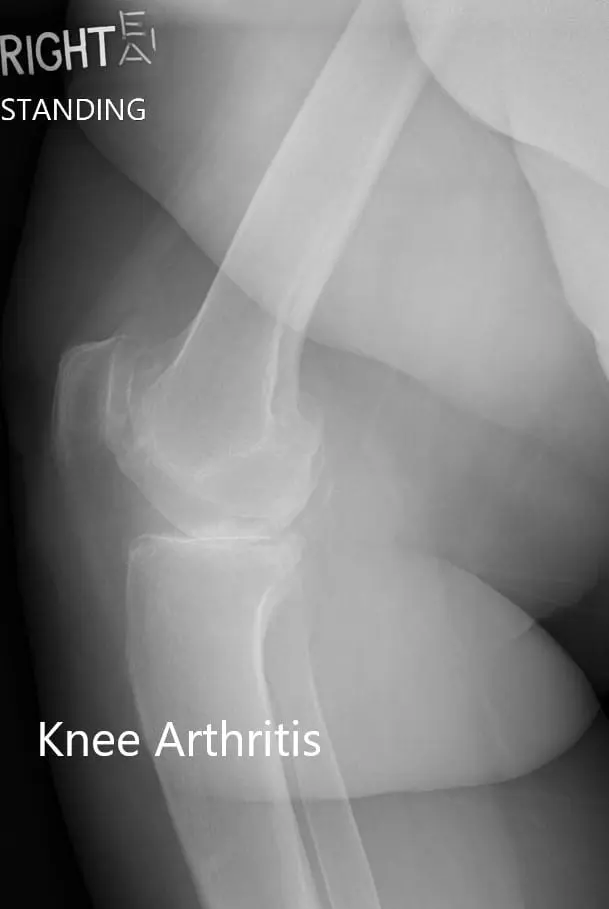

There was no distal neurological deficit. The distal extremity pulses were palpable and comparable. Imaging revealed severe tricompartmental osteoarthritis of the right knee. Options discussed with her at length including surgical and nonsurgical methods. She was given the option of right custom knee replacement. She agreed to go ahead with it.

Preoperative X-ray of the right knee showing AP and lateral views.